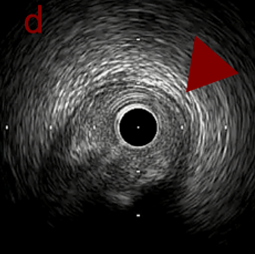

a,b,cはさらに石灰化に食い込み、石灰化量は減少。

それに伴いdではbiasがさらにtentingのIVUS所見にへんかしhigh injury riskと思われた。

引き続き造影で確認してpinpointで引きのOAS high speedを3回さらに追加のためcでIVUSマーキングを行い、その点より引きで赤線のpinpoint OAS high speedを行い、dに関してはinjury回避のためにOASを当てない方針とした。

a,b,cの十分な石灰化のsanding。

High riskのbias所見へと変わっていったdの部位に関してはpinpoint OASを行うことでinjuryなく治療できた。

OASを行うたびに徐々に心筋側側にwire bias変化をきたし、石灰化病変部に関してはそれが良い変化となっているが、distal reference (d) に関してはinjury riskの高いbias変化となっていった。